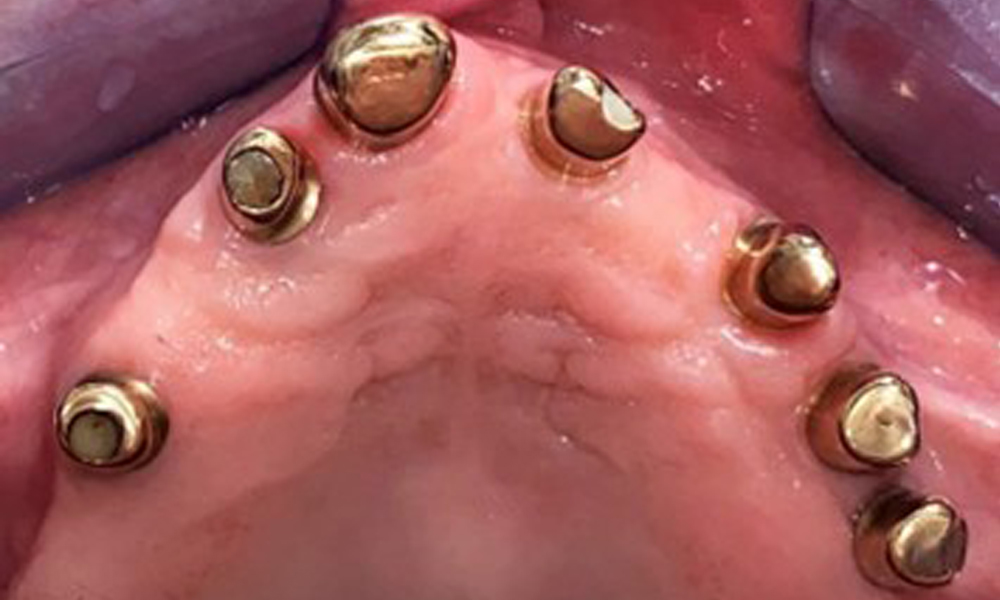

The patient was fitted with a combined removable maxillary telescopic prosthesis more than 25 years ago (Fig. 1, Fig. 2, Fig. 3) and is very happy with her dentures. The patient has an adequate fixed denture for the mandible (Fig. 4).

The dental findings are as follows: Combined removable implant and tooth-supported telescopic prostheses on implants 15, 13, 21, 23, 24, 25 and tooth 11 (Fig. 1, Fig. 2, Fig. 3). The patient was fitted with a fixed mandibular denture. Adequate bridges were present over 37 to 34 and 45 to 47 (Fig. 4), the crown margins were intact and there were no active caries. A composite filling with a marginal gap was present on tooth 43. There was mandibular gingival recession, exposing 1 to 3 mm of root surface. This also applies to 11.

Occlusal view: Maxilla with tooth and implant-supported telescopic prostheses.

Fig. 2: Occlusal view: Maxilla with tooth and implant-supported telescopic prostheses